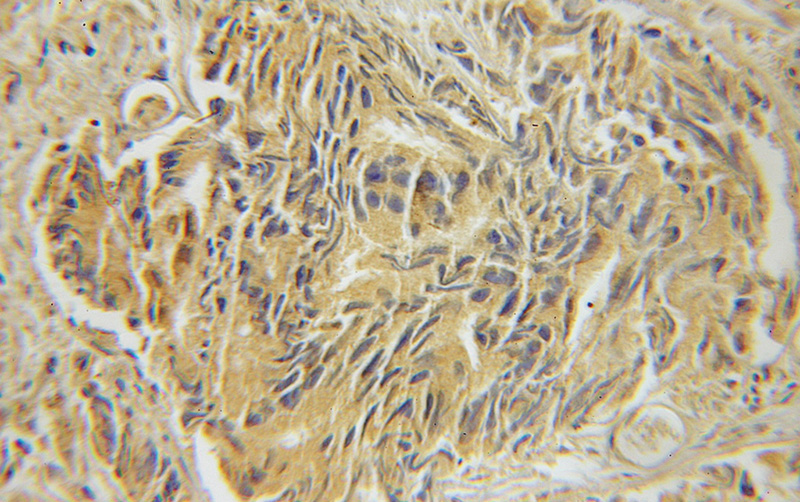

Immunohistochemical of paraffin-embedded human prostate cancer using Catalog No:112449(Marcks antibody) at dilution of 1:200 (under 10x lens)